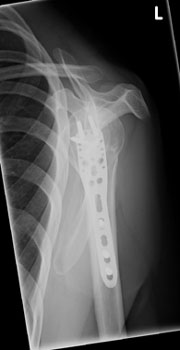

In diesem Fall ist eine winkelstabilen Plattenosteosynthese indiziert. Durch die winkelstabile Schraubenverankerung im Plattenlager und divergierenden Schraubenverlauf, welcher die ganze Breite des Kopffragmentes nutzt, wird eine hohe primäre Stabilität erreicht. Dies ermöglicht eine frühfunktionelle Übungsstabilität bei gleichzeitiger

Schmerzreduktion. |